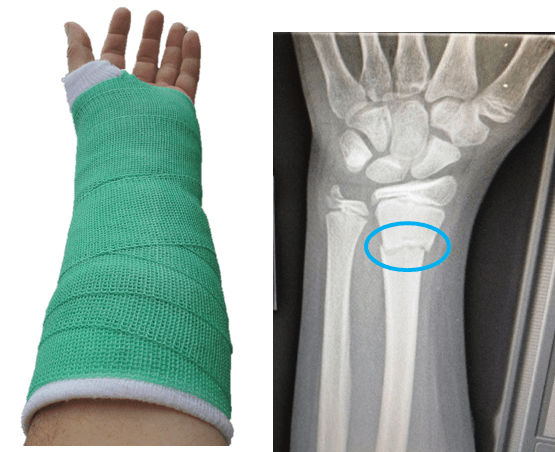

[CLOSED] Sports Engineering PhD Opportunity 2019 – The efficacy of Snowboarding Wrist Guards

Director of Studies: Nick Hamilton (n.hamilton@shu.ac.uk) Summary: CSER has led the way in understanding the efficacy of snowboard wrist guards developing a unique dynamic test and contributing to an international standard which will ensure user safety. The test protocol has been shown to differentiate product performance and the ability to mitigate fracture loadings. CSER are […]